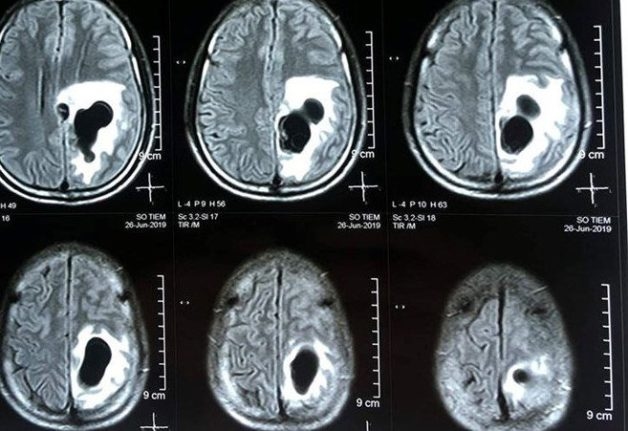

Hình ảnh thu được là các mặt cắt ngang của sọ não sẽ được thể hiện qua hình ảnh trắng đen. Máy MRI cũng có thể chuyển đổi hình ảnh của vùng được khảo sát thành dạng 3D nhằm giúp bác sĩ có thể dễ dàng xác định các bất thường trong não hơn. Chính vì vậy, phương pháp này còn được áp dụng phổ biến trong việc chẩn đoán các bệnh lý thần kinh và não bộ. Chụp cộng hưởng từ não là phương pháp hữu ích giúp phát hiện một số tình trạng của não, bao gồm: tổn thương tủy sống, não úng tủy, sự tích tụ của chất lỏng tủy sống trong các khoang não, chứng phình động mạch hoặc phình mạch máu não trong bệnh đa xơ cứng.

– Hình ảnh chụp MRI có độ tương phản, độ sắc nét cao đem lại hình ảnh chi tiết của các cơ quan rất tốt. Điều này giúp bác sĩ phát hiện tốt những tổn thương hay các vấn đề bất thường liên quan đến mạch máu và não bộ. Từ đó giúp phát hiện chính xác các bệnh lý não bộ như các khối u, nang, xuất huyết, phù nề, nhiễm trùng, chấn thương,… Đây cũng là phương pháp giúp đánh giá và phát hiện sớm nguy cơ đột quỵ, nguyên nhân dẫn đến tử vong hàng đầu hiện nay.

Hình ảnh u não phát hiện qua hình ảnh chụp cộng hưởng từ